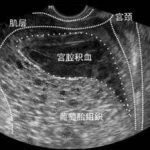

药物流产适用于终止49日以内的妊娠,就是使用药物后身体内的孕酮活力下降,引起流产,再通过药物使子宫发生强烈收缩,迫使妊娠组织排出体外。

药流是通过药物使子宫蜕膜变性坏死、宫颈软化、同时子宫收缩、迫使胚胎排出体外。在这个过程中,患者因子宫收缩自觉下腹部疼痛,这种疼痛感因个人耐受程度不同是有所差异的。